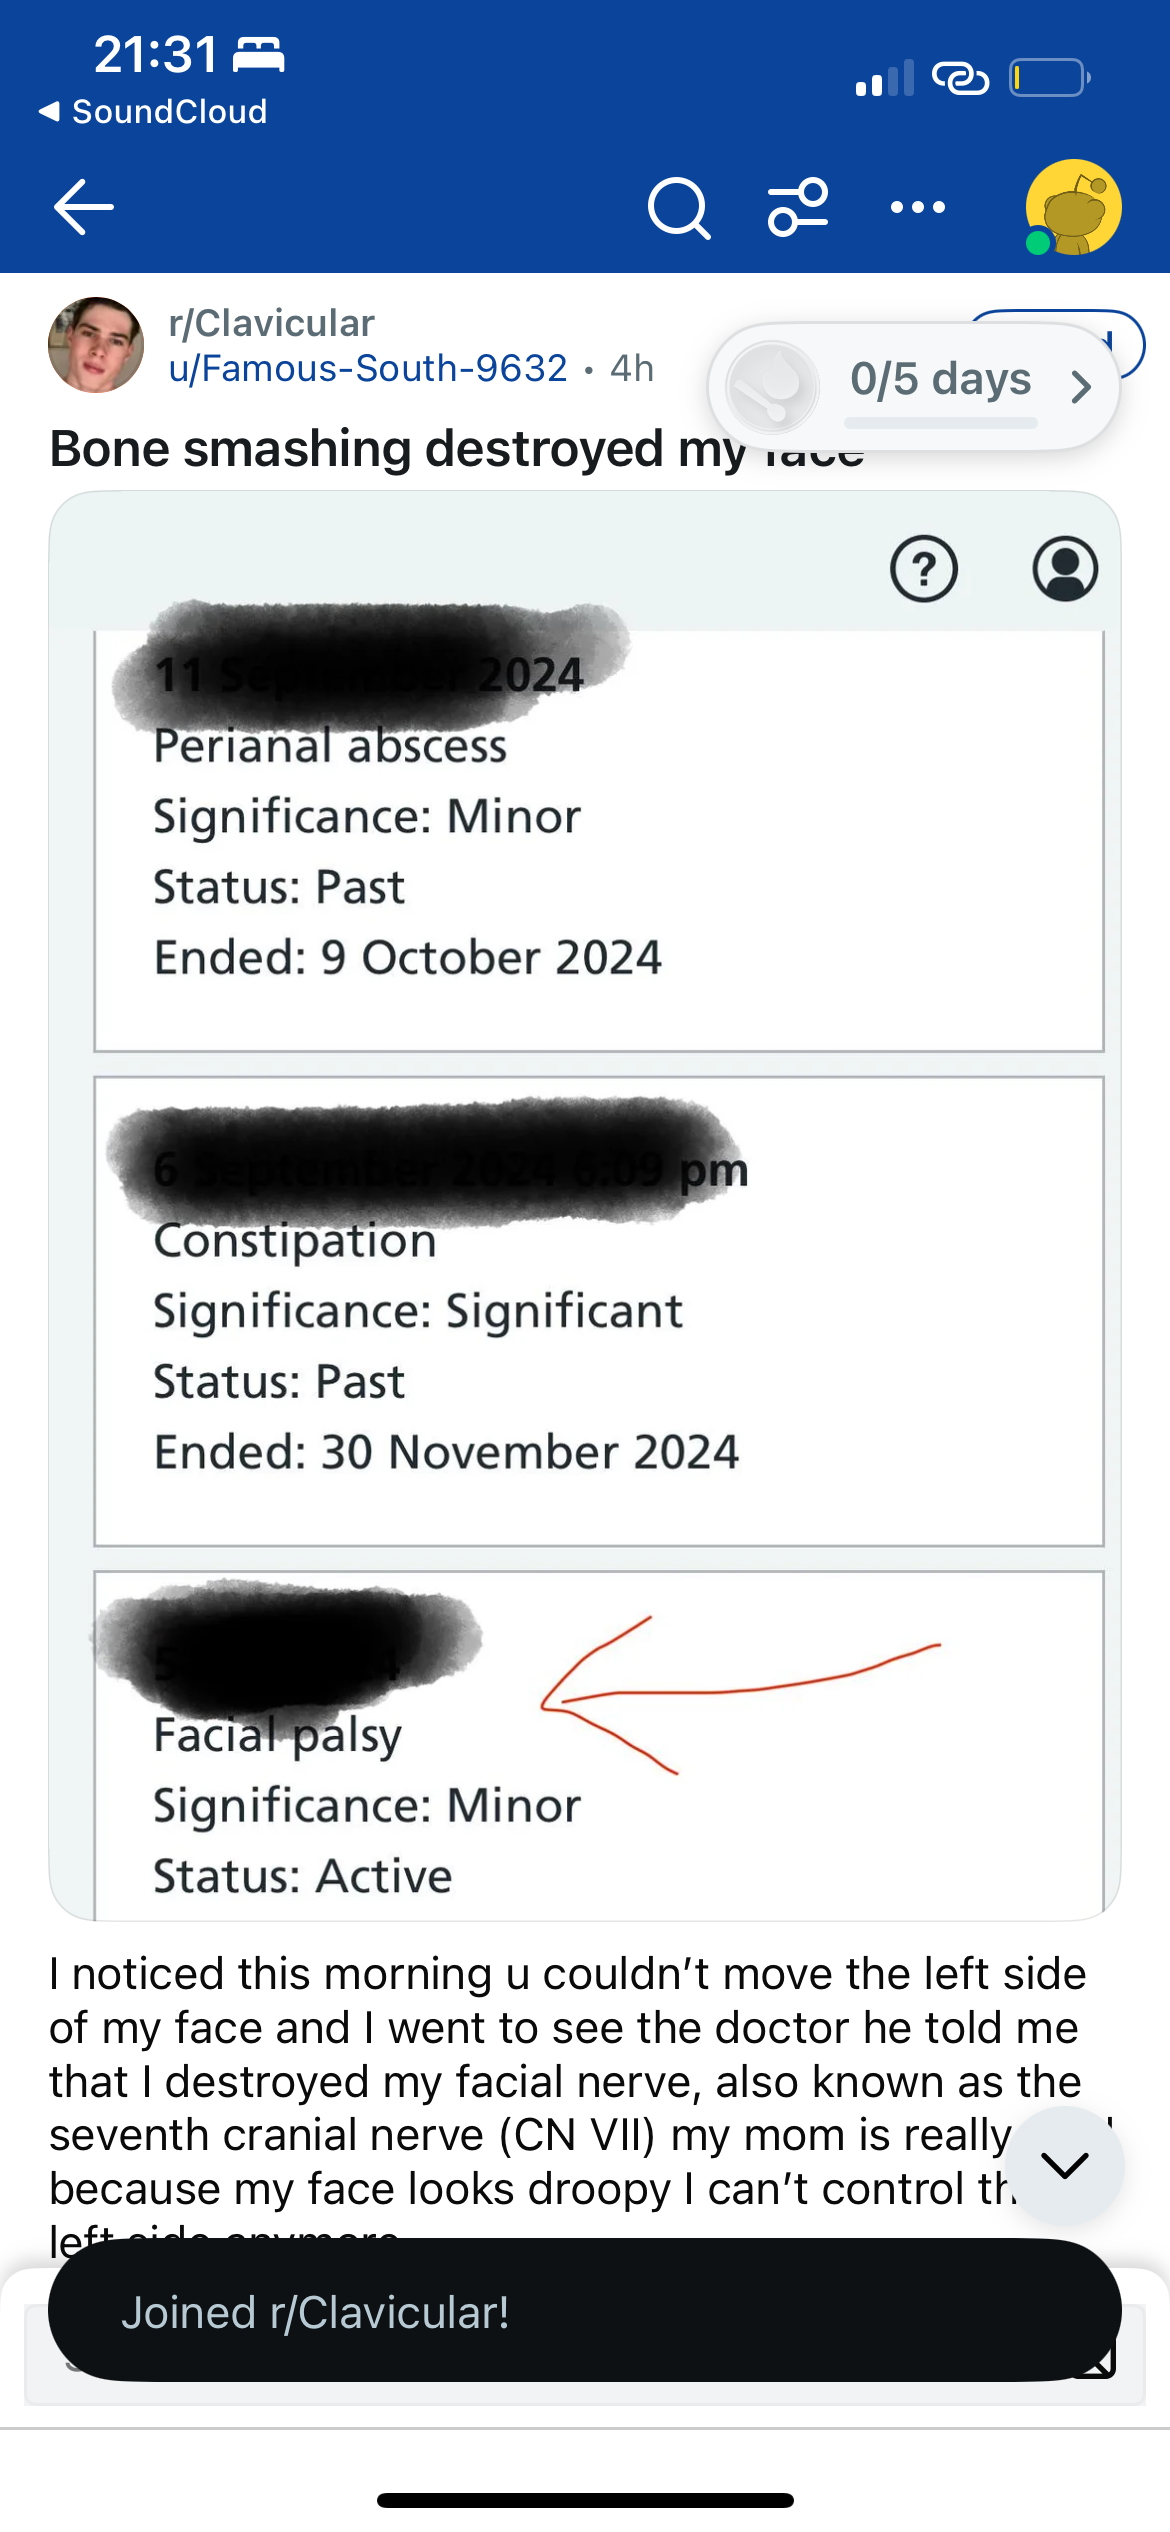

Azie555

True pretty boy gymmaxxer

- Joined

- Jun 8, 2025

- Posts

- 4,396

- Reputation

no way ts real

ts gotta be sum kind of larp bro

Dumb Grey fucked around and found out JFL

if i dont stop will i end up like him? nigga how is it possible hitting a nerve whille smashing ur zygos and chin like ts cant be realYes. You probably should

I mean I'm no doctor. But I'm pretty sure whacking your face with a blunt object isn't very good for your healthif i dont stop will i end up like him? nigga how is it possible hitting a nerve whille smashing ur zygos and chin like ts cant be real

He likely hit his shit HARD with a hammer/something sturdyif i dont stop will i end up like him? nigga how is it possible hitting a nerve whille smashing ur zygos and chin like ts cant be real

I had that once, but wasn’t because of bonesmashing, doctors couldn’t find out why it happened, which is very likely the case here too and It’s just a coincidence that he’s fucking dumb

The kid probably got nerve damage fr ,; but because he is stupid